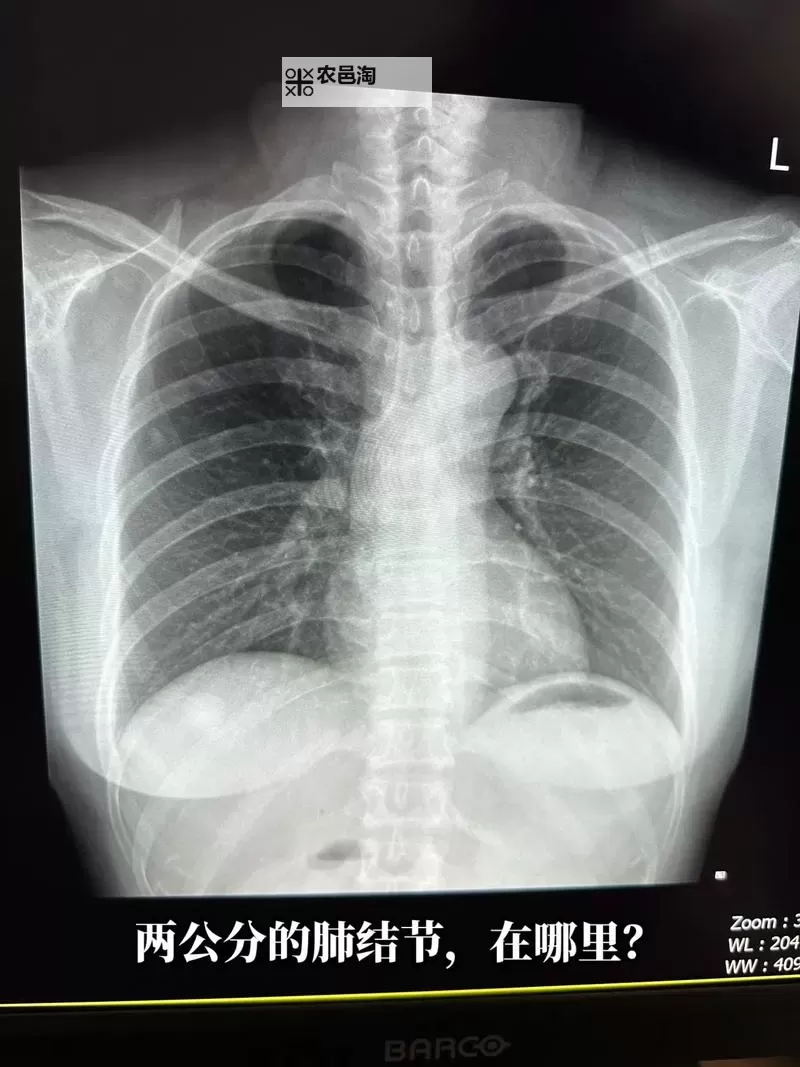

据了解,事件中曝光的胸片中,患者位置明显,因未穿衣服而轮廓清晰。这无疑突破了个人隐私的底线,引发了公众对于隐私保护的强烈愤怒。很多人认为,医疗机构作为公共服务单位,理应严格遵守职业道德和相关法律法规,确保患者隐私不被泄露。这类事件暴露出我国在医疗隐私保护方面仍存在一些制度上的漏洞,也反映出某些医务人员职业操守的不足。